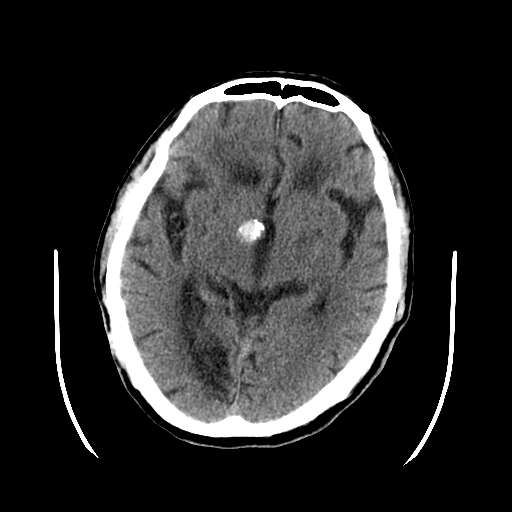

皮脑应该可以诊断,不知道增强病灶有没有强化(ct值),从片上看好像有轻度强化,定位像是脑外的,圆形高密度,内部有点状更高密度考虑为点状钙化,首先考虑为脑膜瘤.鉴别诊断:胶质瘤,垂体瘤,听神经瘤等.

这次病变主要是是因为脑干及小脑的梗塞,另外原有多发脑梗塞。右侧鞍上池及颞叶区可见一大部钙化的病灶,强化后略有增大,并见一条血管进入,考虑血管瘤。不排除脑膜瘤可能!~!

无占位,无水肿带,大部分钙化,av畸形?增强的图片都不尽量在同层面,难比较强化,如果有强化迹象肯定是av畸形!

考虑血管瘤。不排除脑膜瘤及单纯钙化可能!